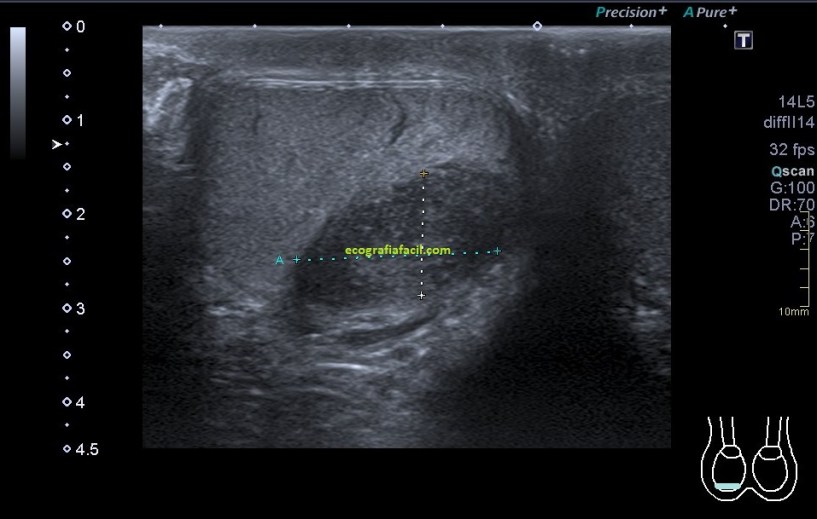

Una vez que hemos encontrado la lesión, es momento de estudiarla detenidamente, su aspecto, tamaño bordes y vascularización son vitales para que la radióloga pueda efectuar un informe.

La imagen 3 y 4 son parte estudian en eje largo y corto las medidas de la lesión en los tres ejes del espacio, en ocasiones, podemos tener más de una lesión. Siempre super atentos si las lesiones son intra o extratesticulares.

El aspecto de esta lesión, su semiología ya la has visto en estos dos casos diferentes, pero tienen en común, de modo general, hipoecogenicidad, heterogenicidad, bordes irregulares, con aspecto polilobulado y de tamaño y número variable.